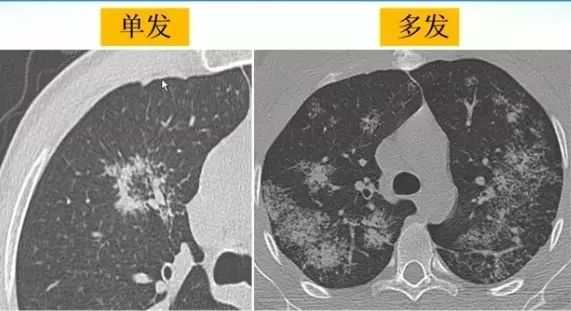

肺内“烟花征”,为活动性肺结核的CT表现之一。是结核经支气管播散并由多发小叶中央结节堆积而成,形态特征似烟花在空中散开。病理基础为细支气管及肺泡内干酪坏死性肉芽肿。